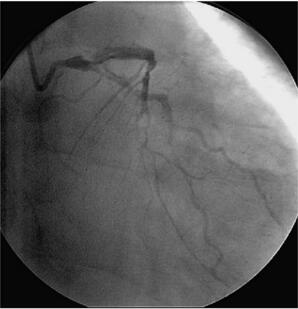

冠状动脉造影(图058‐2、图058‐3)多体位造影显示:冠脉呈右冠优势型,L M开口见90%局限性狭窄;LAD 管壁不光滑,近段见90%局限性狭窄,D1 开口后次全闭塞,中段见85%弥漫性病变,远端血流TI MI 3 级;LCX 管壁不光滑,远端90%局限性狭窄,OM1分叉处Ⅰ型分叉病变,最窄处约80%,远端血流TI MI 3 级;RCA 管壁欠光滑,远段见85%偏心性狭窄,PDA 开口前分叉病变,最窄处约95%,远端血流TI MI 3 级。

图058‐2 冠状动脉造影

图058‐3 冠状动脉造影